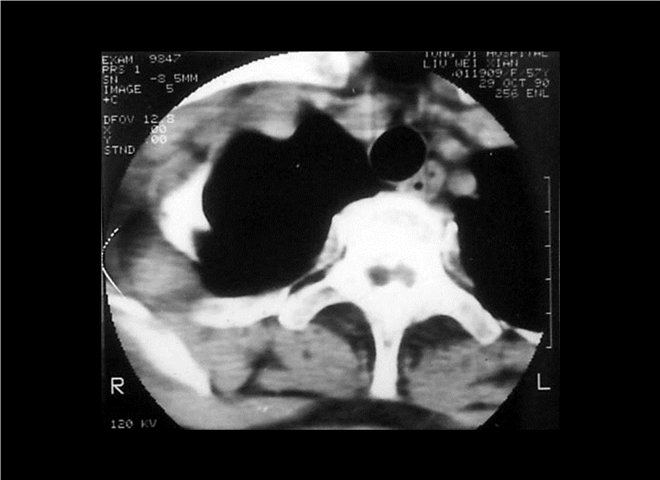

13_CT增强扫描